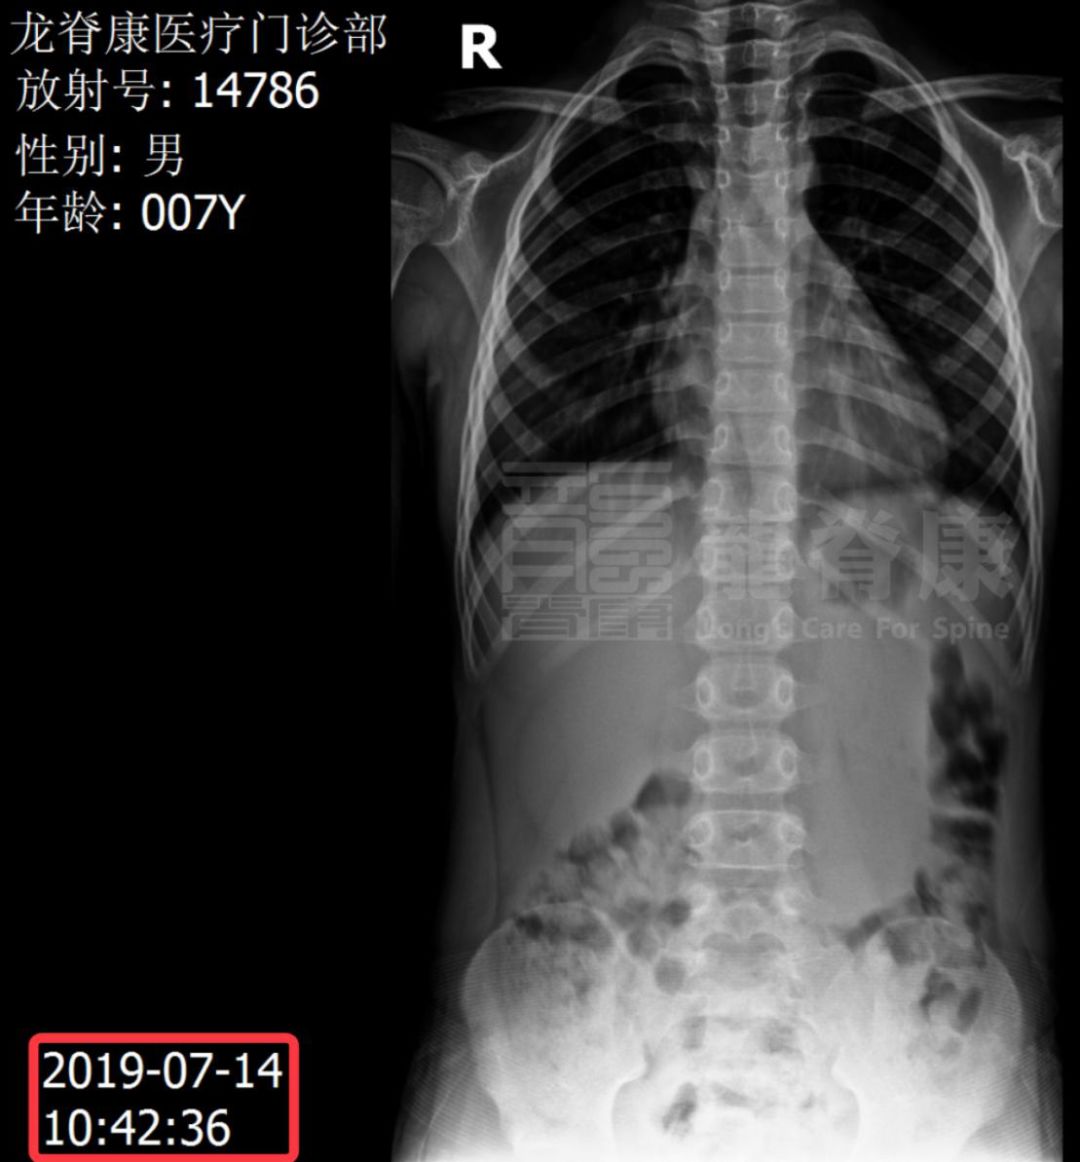

2019-7-14 10:42:36 片示脊柱侧弯消失▽

毅然决定让孩子重新拍片,以确定孩子是否真的患有脊柱侧弯。经第二次X光检查后可见,孩子是没有患脊柱侧弯的,前后两次拍片之所以得出完全不一样的结果,很可能是因为孩子年纪小、好动,拍片时姿势歪扭。